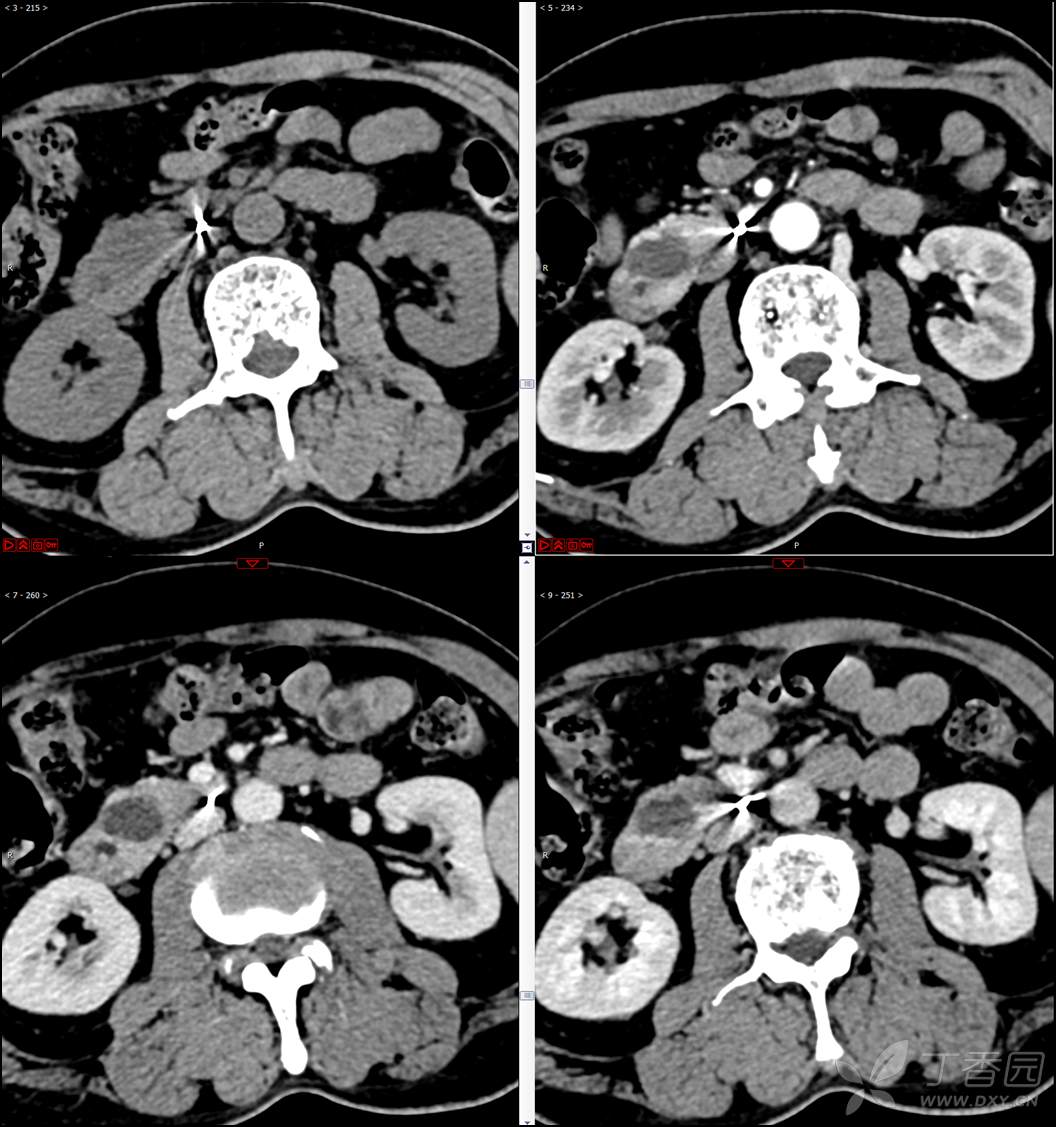

【影诊笔记521】老年男性,黑便就诊,请分析~『回帖即可查阅答案』

患者年龄:67岁

主诉:黑便1周。

现病史:患者1周前无明显诱因出现黑便伴头晕、心慌,无胸闷、胸痛,后仍间断黑便,2022-10-27就诊于某市中医院,行胃镜检查示:十二指肠溃疡伴出血,给予止血、抑酸等对症治疗,效果欠佳。今为行进一步治疗就诊于我院急诊,门诊完善新型冠状病毒核酸检测后以“十二指肠溃疡伴出血”收入我科。患者自发病以来,神志清,精神可,未进食,睡眠可,小便未见异常,黑便,近期体重无明显增减。